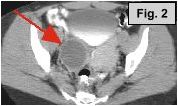

Fig. 1a-c: MRI of the L-spine (sagittal T2 weighted, coronal scout, and coronal MR Myelogram, respectively) demonstrates an incidental 4-5 cm cystic-appearing mass in the right pelvis on limited views of the pelvis. Fig. 2: a helical CT image of the pelvis, revealing a 4x5 cm low-density mass in the right hemipelvis to the right of the uterus. Fig. 3: Pelvic ultrasound shows a moderately enlarged right adnexa measuring 5 cm with low-level echoes.

IMAGING FINDINGS:  Fig. 1a-c show MRI images of the L-spine (sagittal T2 weighted, coronal scout, and coronal MR Myelogram, respectively).  They demonstrate mild scattered disc bulges and an incidental 4-5 cm cystic-appearing mass in the right pelvis on limited views of the pelvis. Incidentally, the MR Myelogram (Fig. 1c) also nicely shows the thecal sac and renal collecting systems.  Fig. 2 shows a helical CT image of the pelvis, revealing a 4x5 cm low-density mass in the right hemipelvis to the right of the uterus with CT density of about 20 Hounsfield units on pre- and post-contrast images.  A repeat transabdominal and endovaginal pelvic ultrasound with Doppler performed at AIC (Fig. 3) showed a moderately enlarged right adnexa measuring 5 cm with low-level echoes.